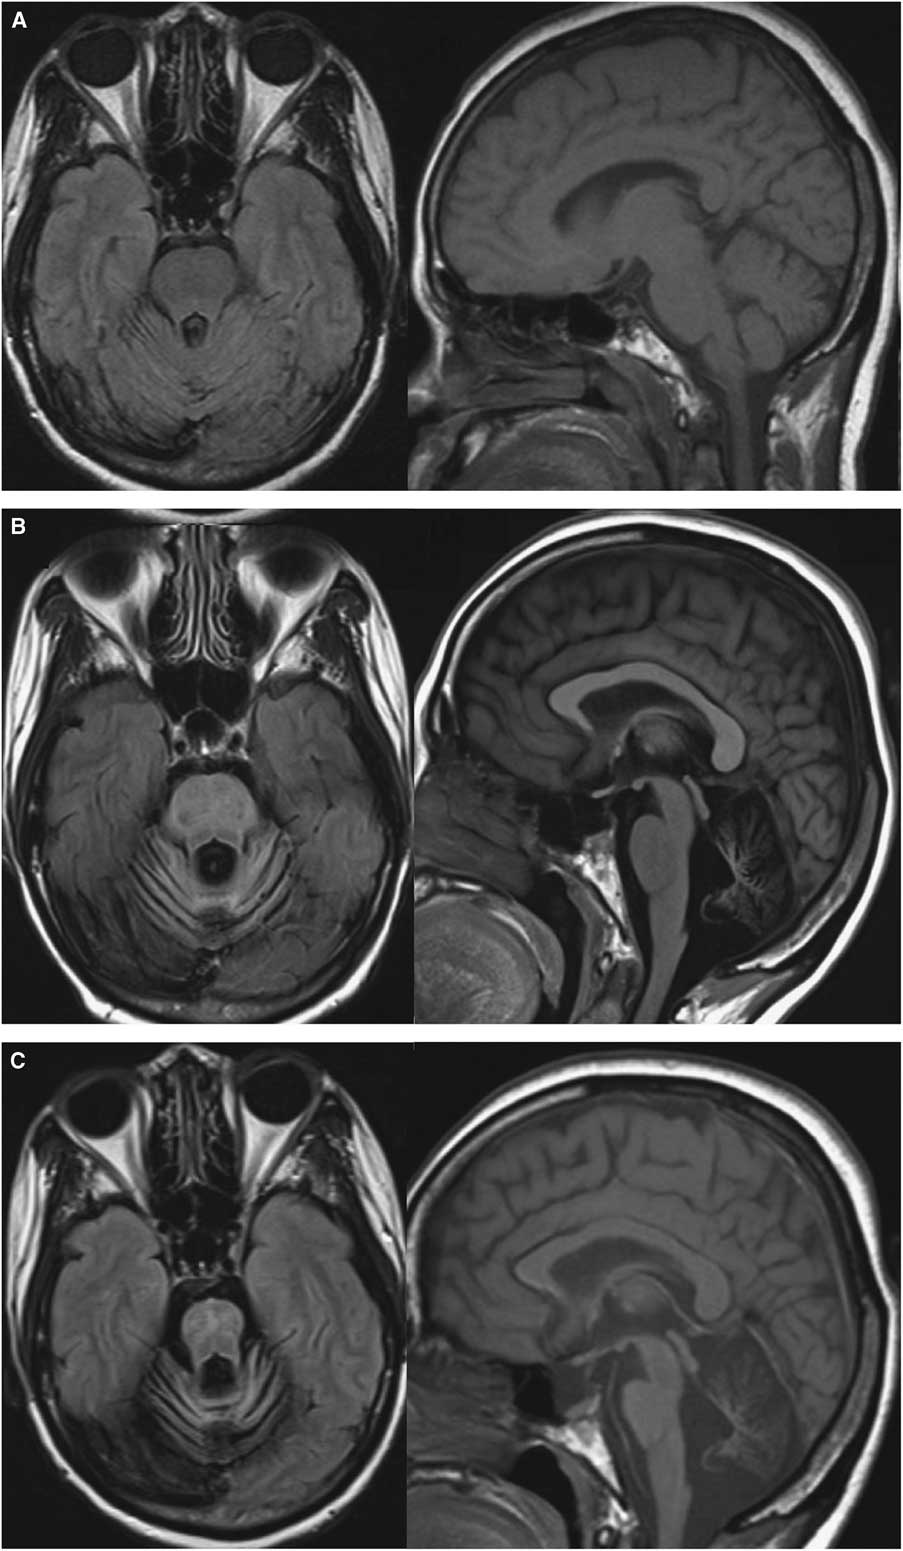

Central nervous system (CNS)-penetrating ART including abacavir/lamivudine and lopinavir/ritonavir was initiated and eventually switched to darunavir/ritonavir. Despite HIV-1 viral load becoming undetectable after 8 weeks and CD4+ lymphocyte count rising to 222 cells/μl, she experienced relentless neurological worsening and cerebellar atrophy (Figure 2). Six months after ART initiation, CSF HIV viral load was undetectable, but JCV remained elevated at 30,000 copies/ml. The absence of gadolinium enhancement or mass effect on MRI and weak JC-virus-specific CD4+ and CD8+ T-cell responses argued against PML immune reconstitution syndrome (PML-IRIS). To investigate this possibility, proton magnetic resonance spectroscopy was proposed, but the patient declined further investigation.

Figure 2 Evolution of MRI abnormalities at (A) 1 month, (B) 10 months and (C) 22 months after symptoms onset. Axial FLAIR sequences showed marked posterior fossa atrophy without signal abnormality (left) and Sagittal T1 sequences showed progressive pontocerebellar and pons atrophy (right).